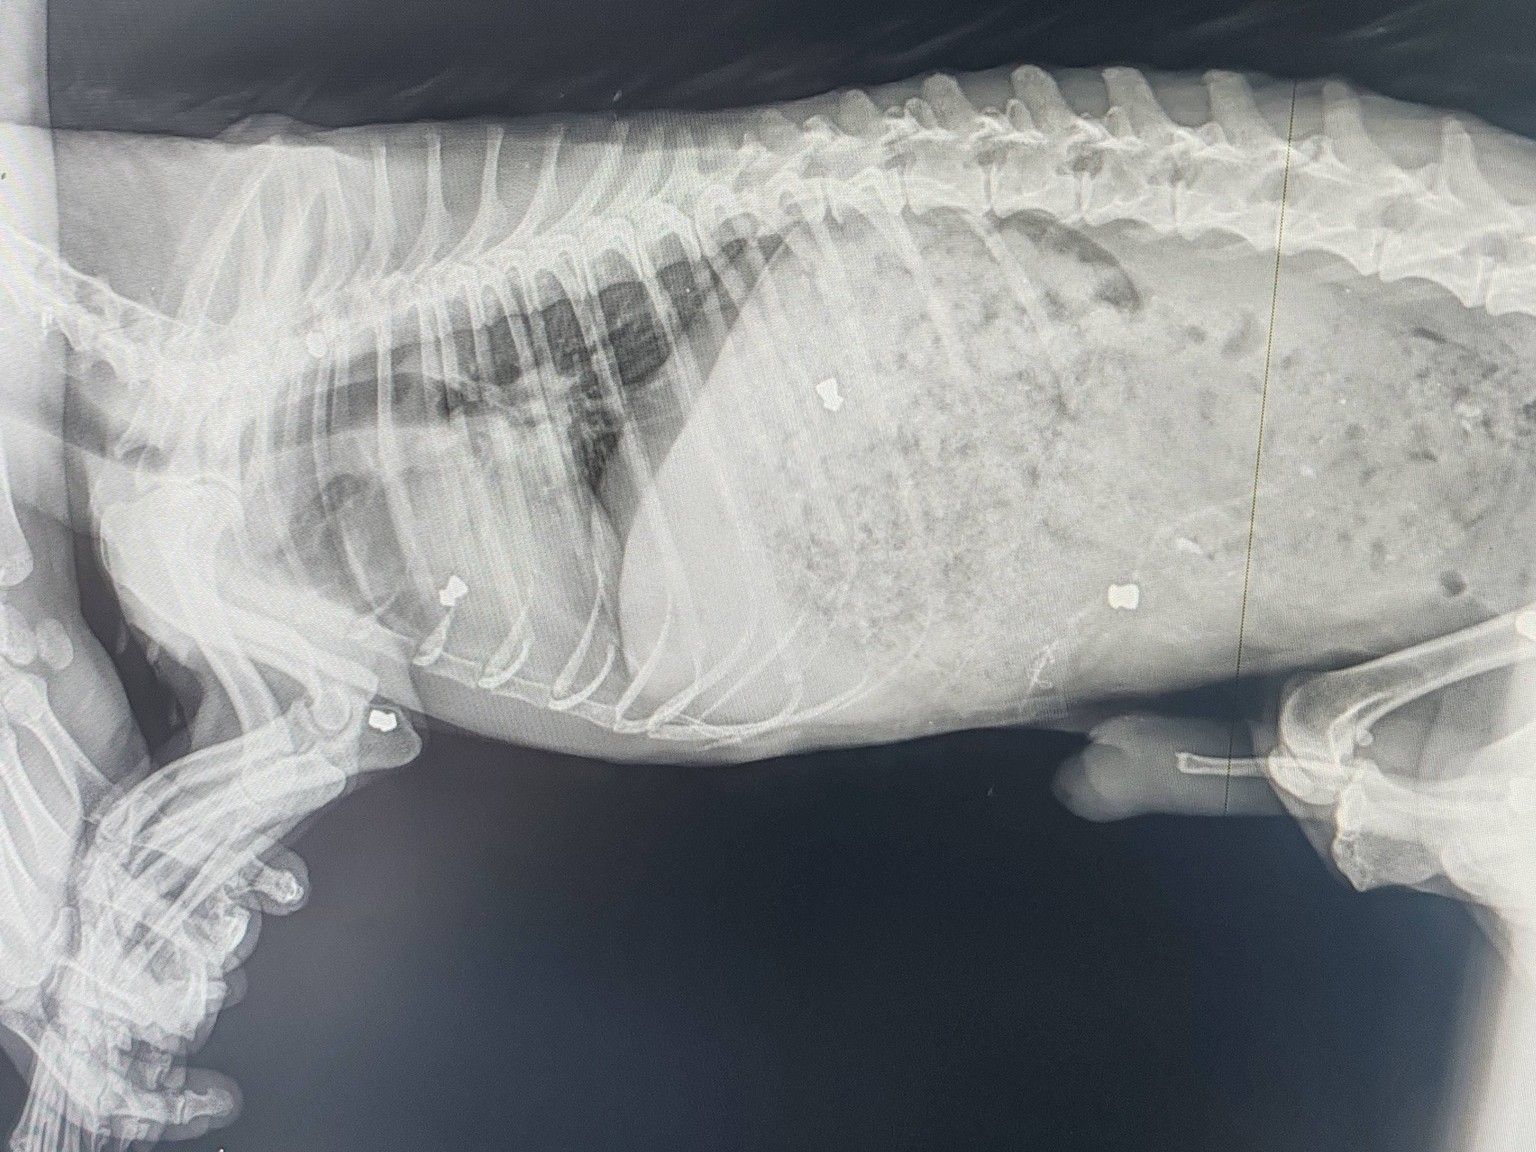

Podľa pracovníčky útulku, Eriky Košovej, bolo už pri prvom kontakte jasné, že psík prežil dlhodobé utrpenie. Ako uviedla pre televíziu JOJ, mal staršiu zlomeninu labky a jeho telo bolo v kŕči od bolesti. Veterinárka Alexandra Hoffmannová následne potvrdila, že v tele zvieraťa našli až sedem diaboliek zo vzduchovky.

Zranenia boli staršieho dátumu a na povrchu neboli viditeľné žiadne rany, čo naznačuje, že psík bol opakovane terčom streľby. „Bol to živý terč,“ uviedla Košová pre televíziu JOJ. Keďže diabolky momentálne nespôsobujú akútne zdravotné komplikácie a psík má približne desať rokov, veterinári ich zatiaľ neplánujú vyberať. Narkóza by pre neho mohla byť riziková.

Okrem strelných poranení trpel psík aj výraznou podvýživou: „Psík je vychudnutý úplne na kosť, no stále mal chuť papať,“ doplnila v reportáži Hoffmannová. Nie je vylúčené, že má aj ďalšie pridružené ochorenia spôsobené dlhodobým zanedbávaním.